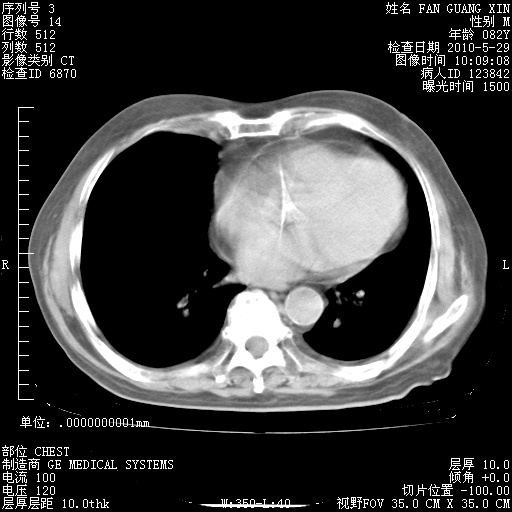

再治疗10天后的肺部CT

再治疗10天后的肺部CT 纵膈窗

阅读此次胸部CT,肺间质渗出性改变较入院时有吸收。目前从体温、白细胞、中性分叶明显增高,肯定存在细菌感染(发生医院感染哦,若无消化道及泌尿系统等感染的依据,肺部感染可能大)。若你院头孢哌酮舒巴坦钠耐药率较高,同意你的方案,若48小时体温仍高,可考虑使用碳青霉稀类抗菌药物,同时可予超声雾化、注意滴数时加大液体量。白蛋白33.30g/L较低哦,需加强营养等支持治疗。